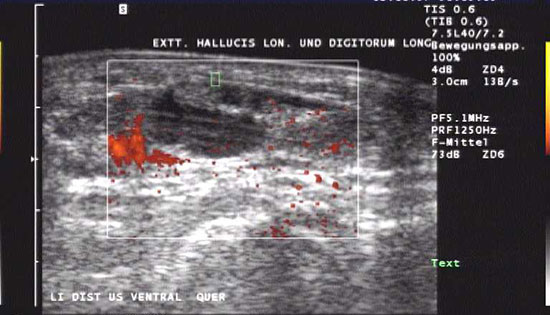

Sonographie

Die sonographische Untersuchung des Fußes wird in der Regel mit 7,5MHz durchgeführt. Erfasst und differenziert werden können ein Gelenkerguss bei Synovialitis, eine Bursitis bzw. eine Tenosynovialitis. Mit Hilfe des Power-Dopplers kann auch eine Aussage über die Krankheitsaktivität gemacht werden.

Flüssigkeit und erhöhte Gewebeperfusion im Powerdoppler sind Kennzeichen der rheumatoiden Arthritis im Ultraschall. Hier zeigt sich die Entzündung um die Extensor hallucis longus Sehne.

Abbildung 3